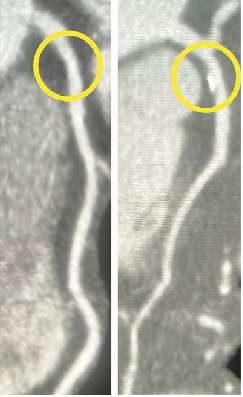

如下图一名 58 岁自述胸痛的女性的心脏 CT 扫描结果,

左图基线 CT 扫描显示左前降支动脉近端没有斑块(圆圈)。5 年后的 CT 扫描(右图)显示左前降支动脉近端有斑点状钙化的混合斑块(圆圈)。

PARADIGM研究显示显示,

相较于非阻塞性病变而言,斑块的进展程度可能是导致心肌梗死发生的更重要因素。